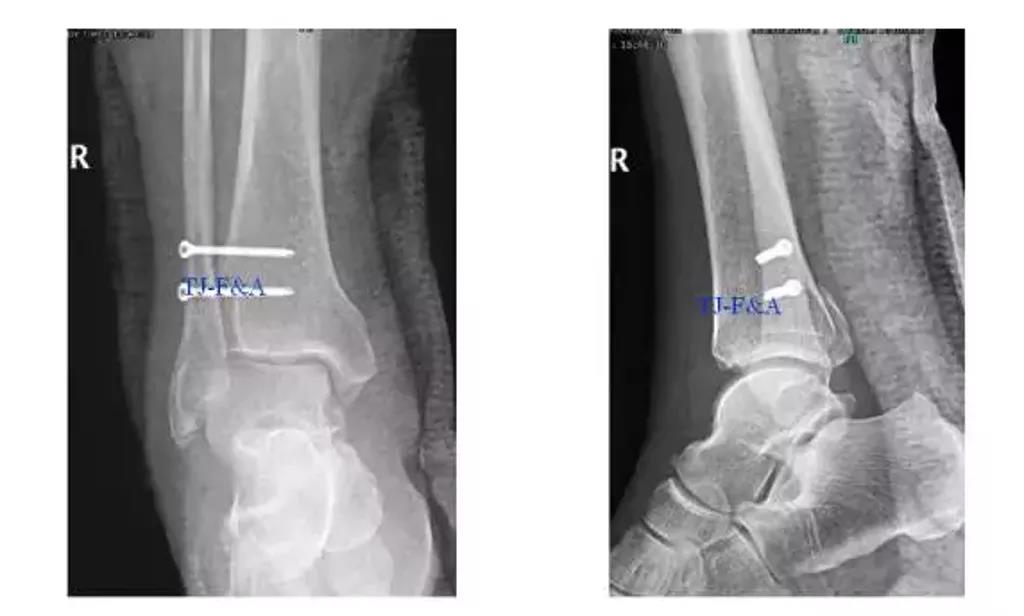

术后DR

术前DR

术中:

术后2个月: